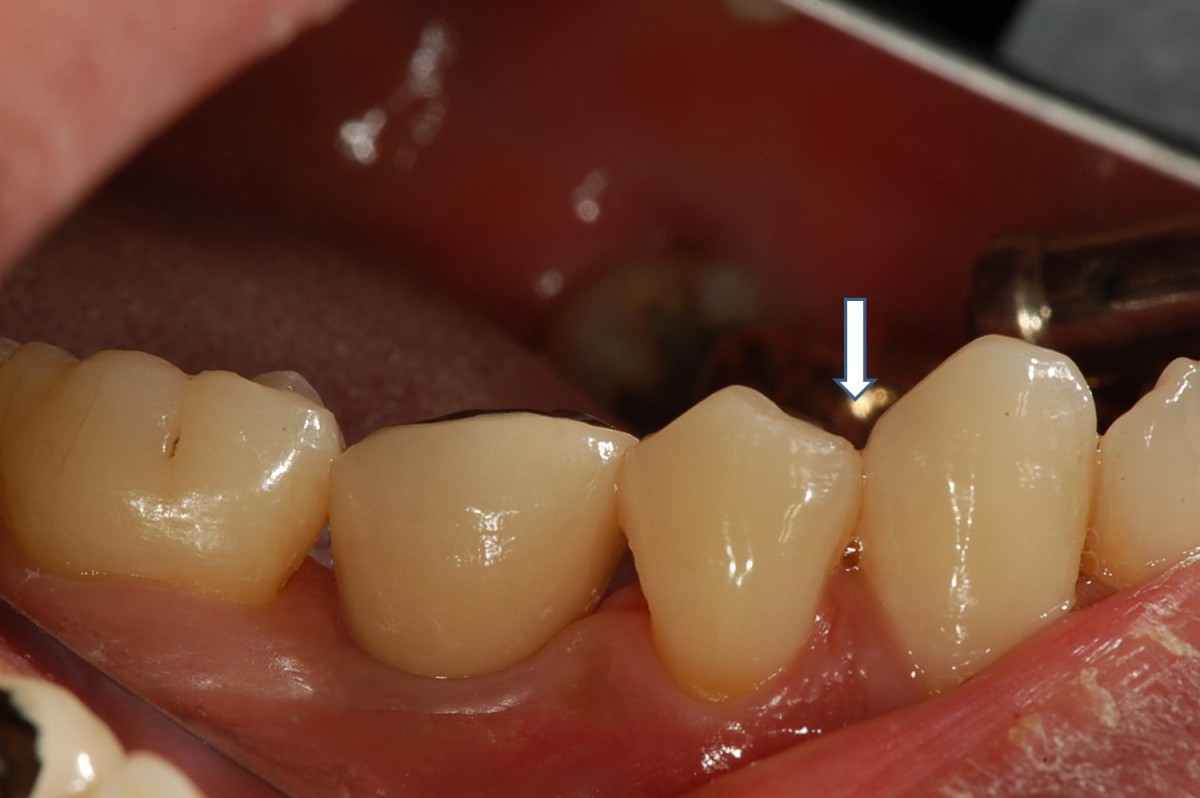

▲Remaining promary tooth